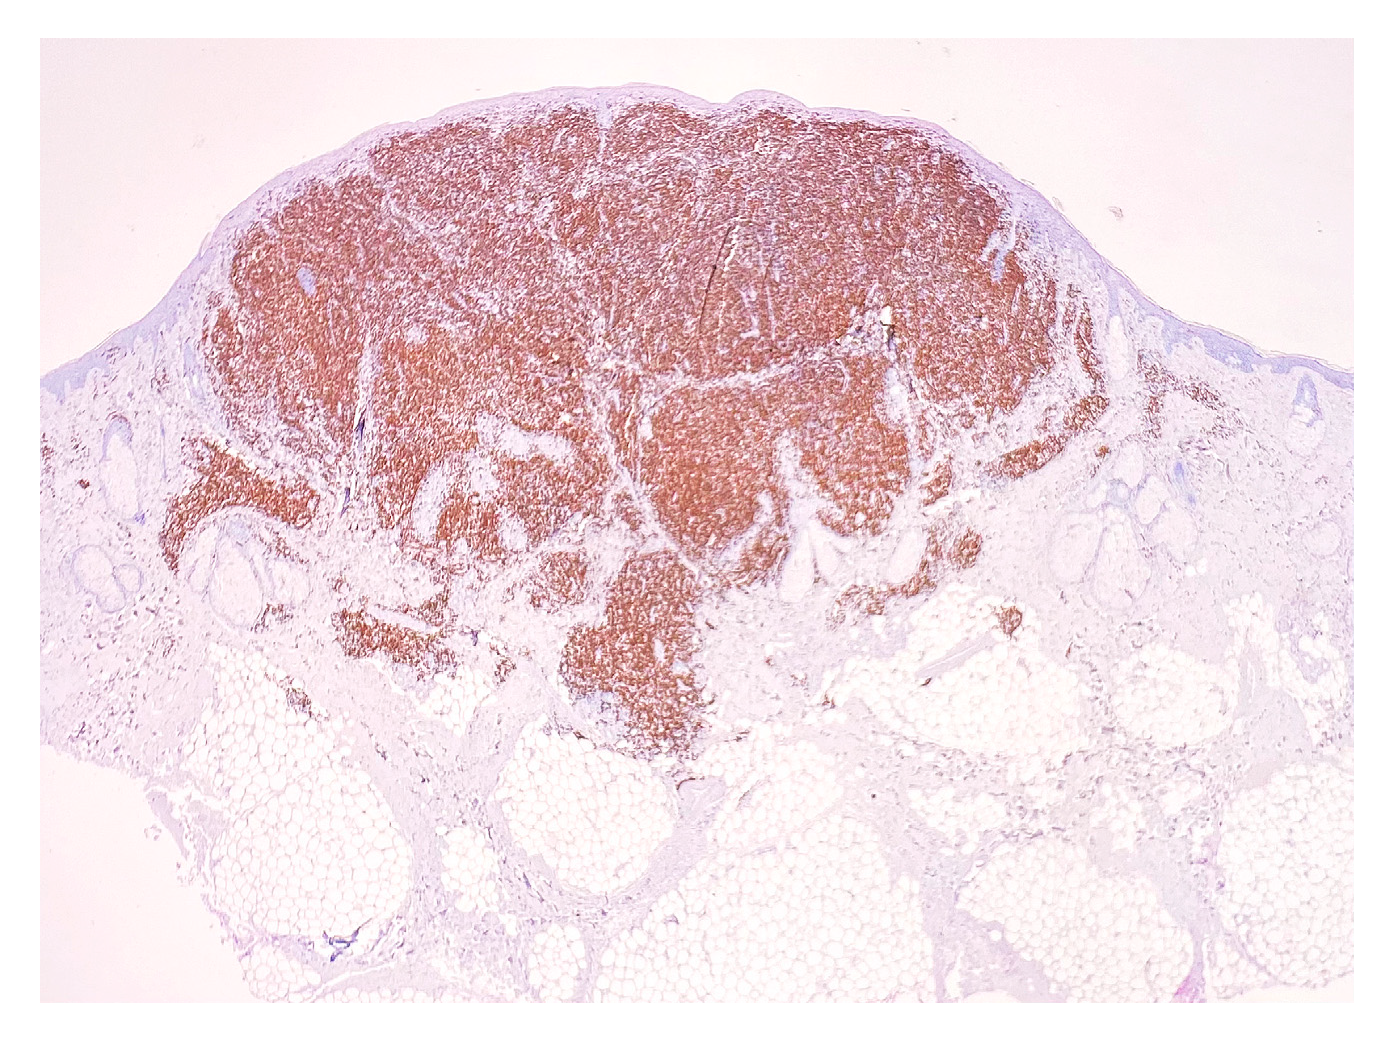

| Antibody | Clone | Producer | Pretreatment | Dilution |

|---|---|---|---|---|

| CD3 | MRQ-39 | Cell Marque | HIER EDTA 19 min | 1:100 |

| CD4 | EP204 | Cell Marque | HIER EDTA 19 min | 1:200 |

| CD8 | C8/144B | Cell Marque | HIER EDTA 19 min | 1:200 |

| CD20 | L26 | Cell Marque | HIER EDTA 19 min | 1:100 |

| CD30 | Ber-H2 | Bio SB | HIER EDTA 19 min | 1:100 |

| Ki67 | MIB-1 | DAKO | HIER EDTA 19 min | 1:200 |

| PD1 | NAT105 | Cell Marque | HIER EDTA 19 min | 1:100 |